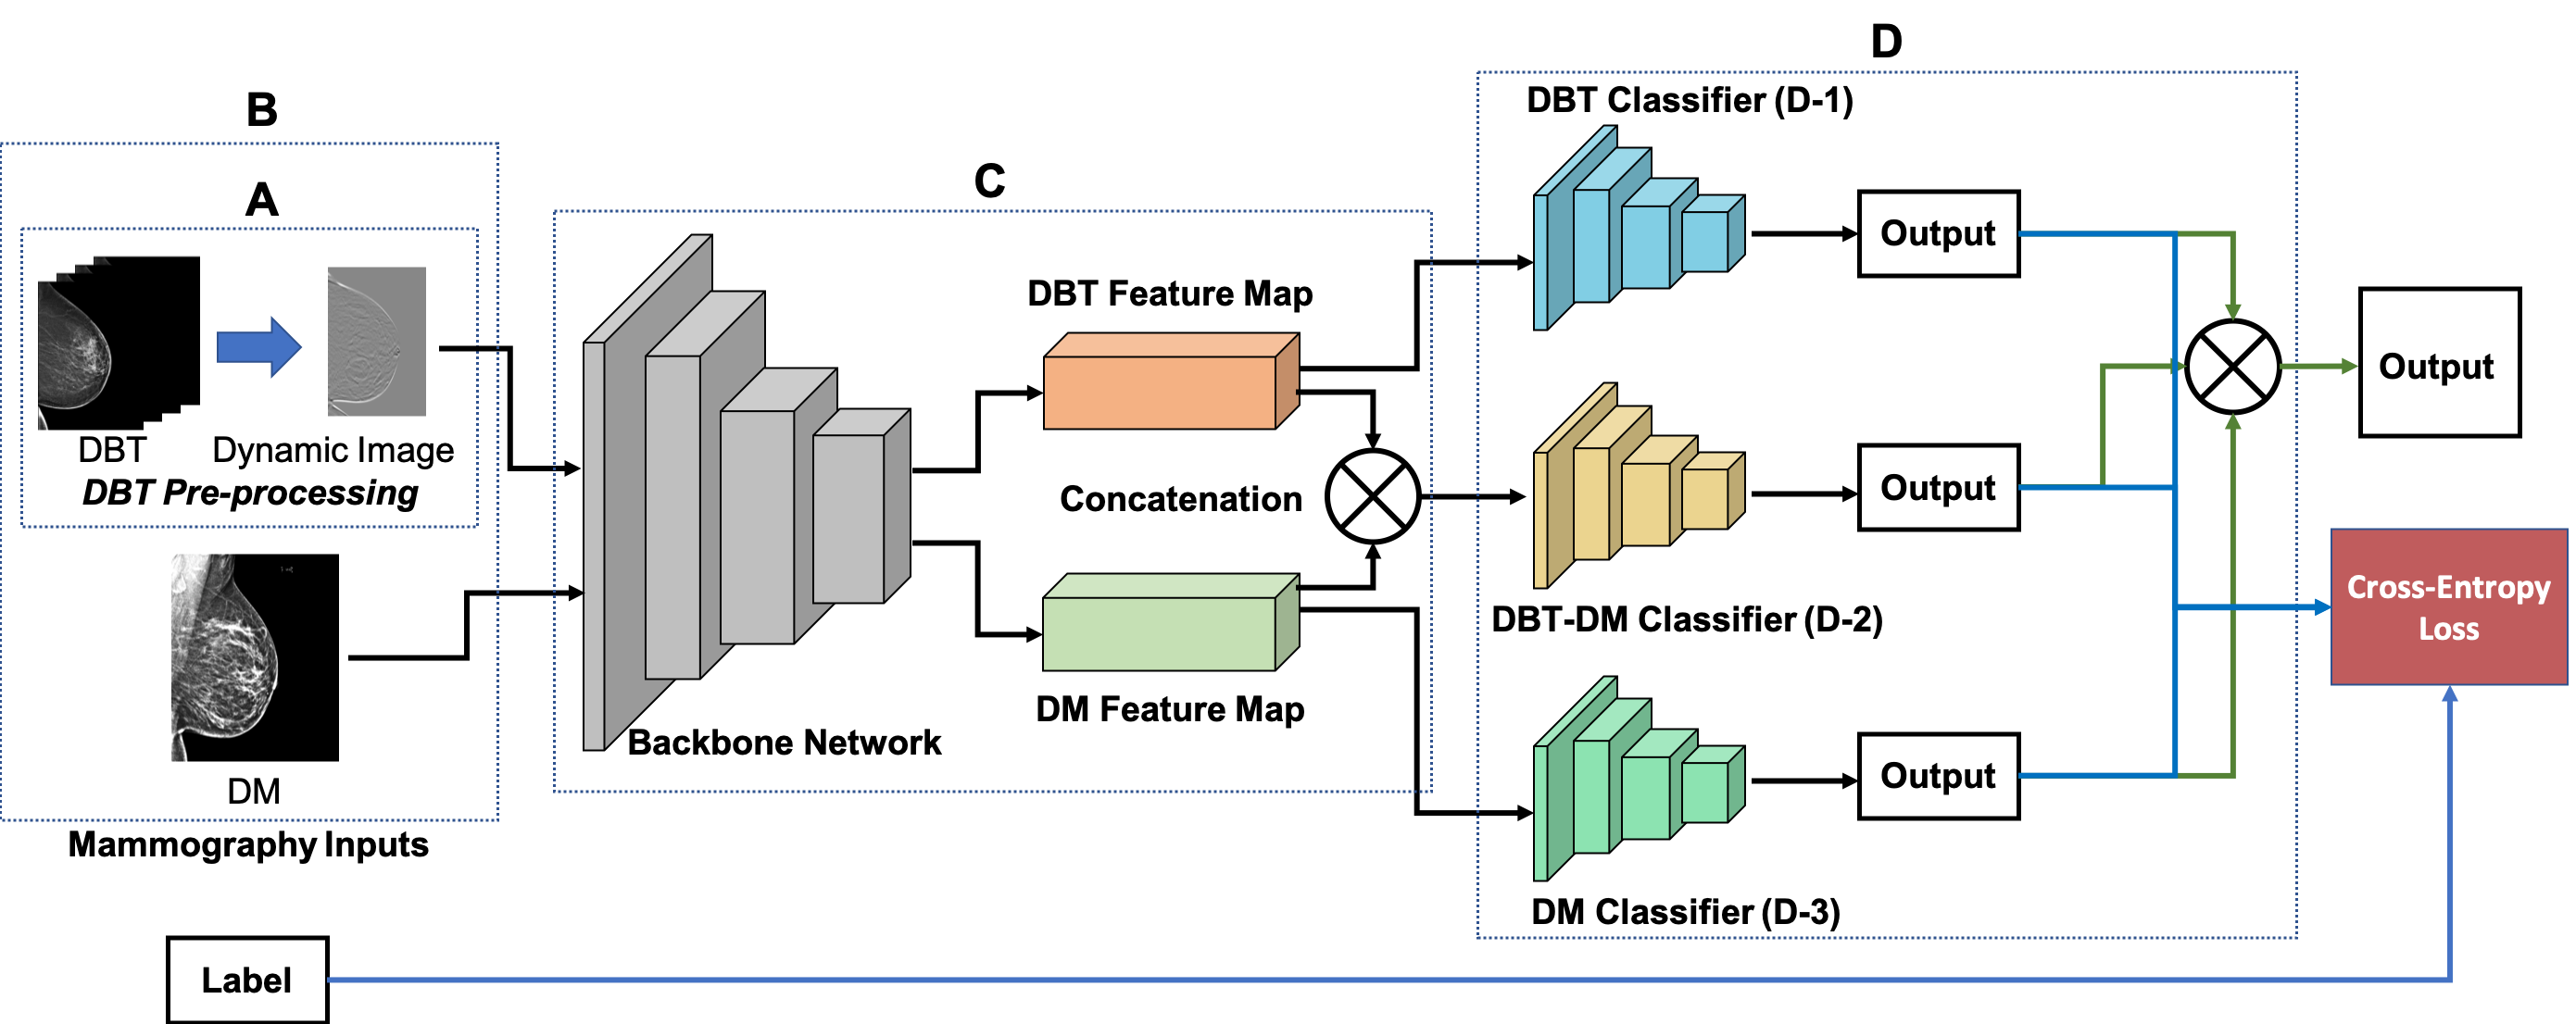

We propose a novel CNN ensemble method for breast tumor classification. The proposed approach consists of three main components: 1) DBT pre-processing approach (Figure 1A), 2) DBT and DM feature extraction and feature map concatenation (Figure 1C), and 3) multiple classifiers and ensemble outputs of each classifier (Figure 1D).

The proposed network contains two kinds of CNNs: the backbone CNN feature extracting network (feature extractor) and the shallow CNN classifier (classifier).

III-B2 CNN Classifier

There are three CNN classifiers with two different architectures included in the proposed model. The DBT Classifier and DM Classifier (Figure 1D-1 and 1D-3) are used for DBT feature map classification and DM feature map classification, respectively. These two classifiers share the same architecture but with different weights, which was implemented as a 2D Conv layer followed by two FC layers. The DM-DBT Classifier (Figure 1D-2) simultaneously evaluates the DM and DBT by taking the feature maps of the two imaging modality in combination. Since we concatenated the two feature maps on the dimension, the dimensionality of the feature map is increased by (see Figure 3). We replace the 2D Conv layer in the other classifiers with a 3D Conv layer. The 3D Conv kernels are applied on the , , and dimensions. Both of the 2D and 3D Conv layer included convolution, batch normalization, leaky ReLU, and max pooling. The batch size is . Max pooling has a or receptive field with stride for 2D or 3D Conv layer, respectively. Cross-entropy loss is used in training. Adam optimizer with a learning rate of is used as the optimizer. Dropout with a rate of is applied to the FC layers. See Table I for Classifier architecture detail.